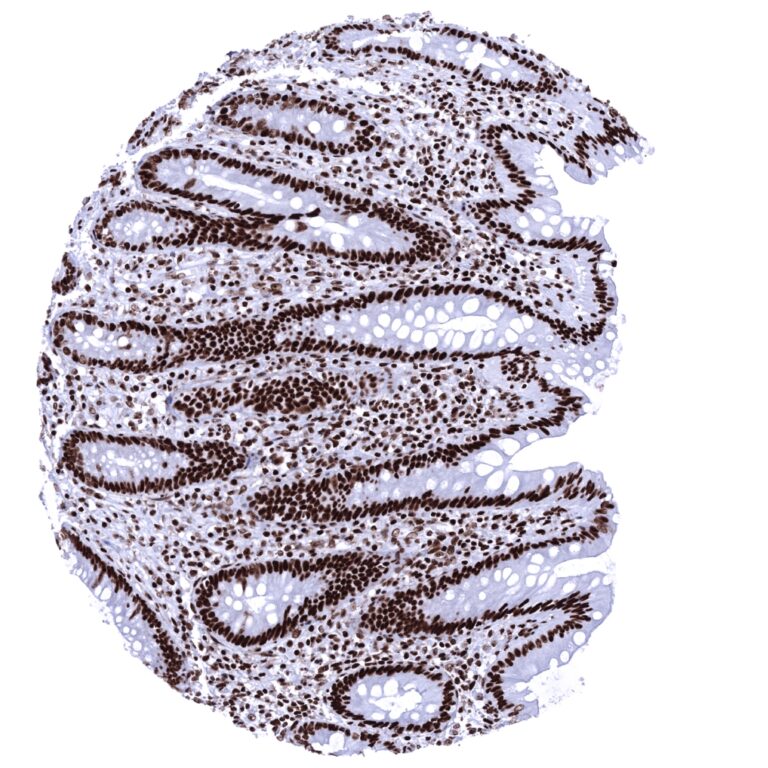

Staining Pattern in Normal Tissues

Ku80 immunostaining occurs in virtually all nuclei of all cells in all tissues. Variations of the staining intensity are hardly discernible. A reduced level of expression is, however, seen in hepatocytes and spermatids. Cytoplasmic and/or membranous Ku80 immunostaining is not seen in any normal striated muscle, heart muscle, smooth muscle, myometrium of the uterus, corpus spongiosum of the penis, ovarian stroma, fat, skin (including hair follicle and sebaceous glands), oral mucosa of the lip, oral cavity, surface epithelium of the tonsil, and transitional mucosa of the anal canal, ectocervix, squamous epithelium of the esophagus, urothelium of the renal pelvis and urinary bladder, decidua, placental trophoblastic cells, lymph node, spleen, thymus, tonsil, mucosa of the stomach, duodenum, ileum, appendix, colon, rectum and gall bladder, pancreas, liver, parotid gland, submandibular gland, sublingual gland, Brunner gland of the duodenum, cortex and medulla of the kidney, prostate, seminal vesicle, epididymis, testis, respiratory epithelium and glands of bronchi and paranasal sinus, lung, breast, endocervix, endometrium, fallopian tube, corpus luteum and follicular cyst of the ovary, adrenal gland, parathyroid gland, cerebellum, cerebrum and pituitary gland.

Nuclear Ku80 immunostaining is seen in the vast majority of tumors although the intensity may vary considerably between individual cases.